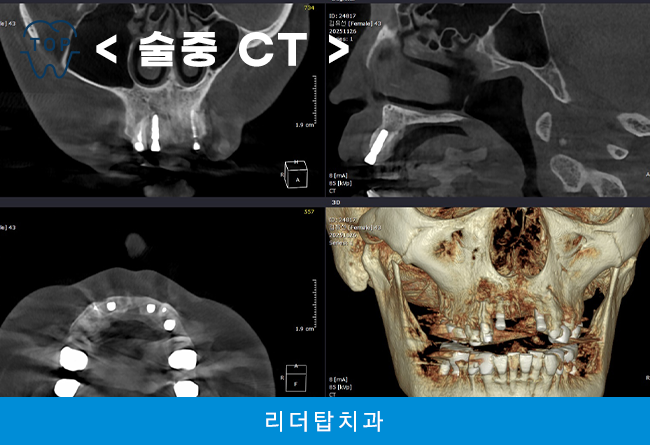

다수의 임플란트를 진행할 때에는 잇몸뼈 상태에 따라 크게 좌우되는데 치아 상실 후 시간이 지나면 치조골이 점차 흡수되어 골의 높이와 폭이 줄어들 수 있으며, 이 경우 단순 식립만으로는 치료가 어려워 뼈이식이나 상악동 거상술 등 보조 술식이 필요할 수 있습니다. 이에 따라 3D CT 촬영을 통해 골의 양과 밀도, 신경 위치 등을 정밀하게 파악하는 과정이 치료의 기본 단계로 꼽힙니다.

먼저 예후가 좋지 않은 자연치들을 발치하고 어금니 부위부터 임플란트 식립 후, 앞니까지 식립을 완료하였습니다.

특히 앞니의 경우 잇몸뼈의 두께가 얇고 치아 뿌리 방향이나 잇몸선의 높낮이가 외관에 그대로 드러나는 특징이 있어 식립 각도나 위치가 조금만 어긋나도 치아 길이가 부자연스럽게 보이거나 잇몸 경계가 비대칭으로 형성될 수 있습니다. 웃을 때 잇몸이 많이 드러나는 경우에는 임플란트 주변 잇몸 형태가 치료 결과의 만족도를 크게 좌우합니다. 더불어 중요한 요소 중 하나는 잇몸뼈의 상태로 치아를 상실한 뒤 시간이 지나면 해당 부위의 뼈가 흡수되는 경향이 있는데 앞니 부위는 이러한 변화가 외형에 더 민감하게 반영되므로 CT 검사를 통해 뼈의 높이와 폭, 잇몸 두께를 면밀히 확인하는 과정이 필요합니다.